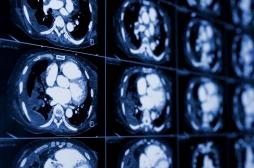

cancer du rein